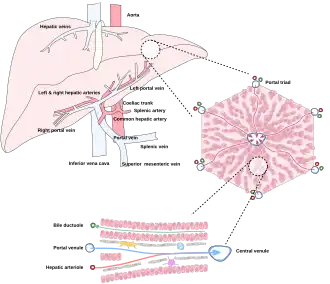

The liver is connected to two large blood vessels: the hepatic artery and the portal vein. The hepatic artery carries oxygen-rich blood from the aorta via the celiac trunk, whereas the portal vein carries blood rich in digested nutrients from the entire gastrointestinal tract and also from the spleen and pancreas.[11] These blood vessels subdivide into small capillaries known as liver sinusoids, which then lead to hepatic lobules.

Microscopically, each liver lobe is seen to be made up of hepatic lobules. The lobules are roughly hexagonal, and consist of plates of hepatocytes, and sinusoids radiating from a central vein towards an imaginary perimeter of interlobular portal triads.[24] The central vein joins to the hepatic vein to carry blood out from the liver. A distinctive component of a lobule is the portal triad, which can be found running along each of the lobule's corners. The portal triad consists of the hepatic artery, the portal vein, and the common bile duct.[25] The triad may be seen on a liver ultrasound, as a Mickey Mouse sign with the portal vein as the head, and the hepatic artery, and the common bile duct as the ears.[26]

The liver gets its blood supply from the hepatic portal vein and hepatic arteries. The hepatic portal vein delivers around 75% of the liver's blood supply and carries venous blood drained from the spleen, gastrointestinal tract, and its associated organs. The hepatic arteries supply arterial blood to the liver, accounting for the remaining quarter of its blood flow. Oxygen is provided from both sources; about half of the liver's oxygen demand is met by the hepatic portal vein, and half is met by the hepatic arteries.[46] The hepatic artery also has both alpha- and beta-adrenergic receptors; therefore, flow through the artery is controlled, in part, by the splanchnic nerves of the autonomic nervous system.

Blood flows through the liver sinusoids and empties into the central vein of each lobule. The central veins coalesce into hepatic veins, which leave the liver and drain into the inferior vena cava.[47]

The biliary tract is derived from the branches of the bile ducts. The biliary tract, also known as the biliary tree, is the path by which bile is secreted by the liver then transported to the first part of the small intestine, the duodenum. The bile produced in the liver is collected in bile canaliculi, small grooves between the faces of adjacent hepatocytes. The canaliculi radiate to the edge of the liver lobule, where they merge to form bile ducts. Within the liver, these ducts are termed intrahepatic bile ducts, and once they exit the liver, they are considered extrahepatic. The intrahepatic ducts eventually drain into the right and left hepatic ducts, which exit the liver at the transverse fissure, and merge to form the common hepatic duct. The cystic duct from the gallbladder joins with the common hepatic duct to form the common bile duct.[47] The biliary system and connective tissue is supplied by the hepatic artery alone.